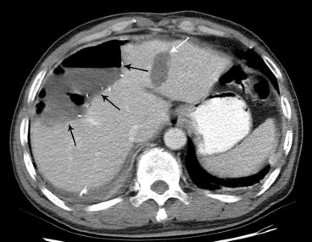

Fig. 2